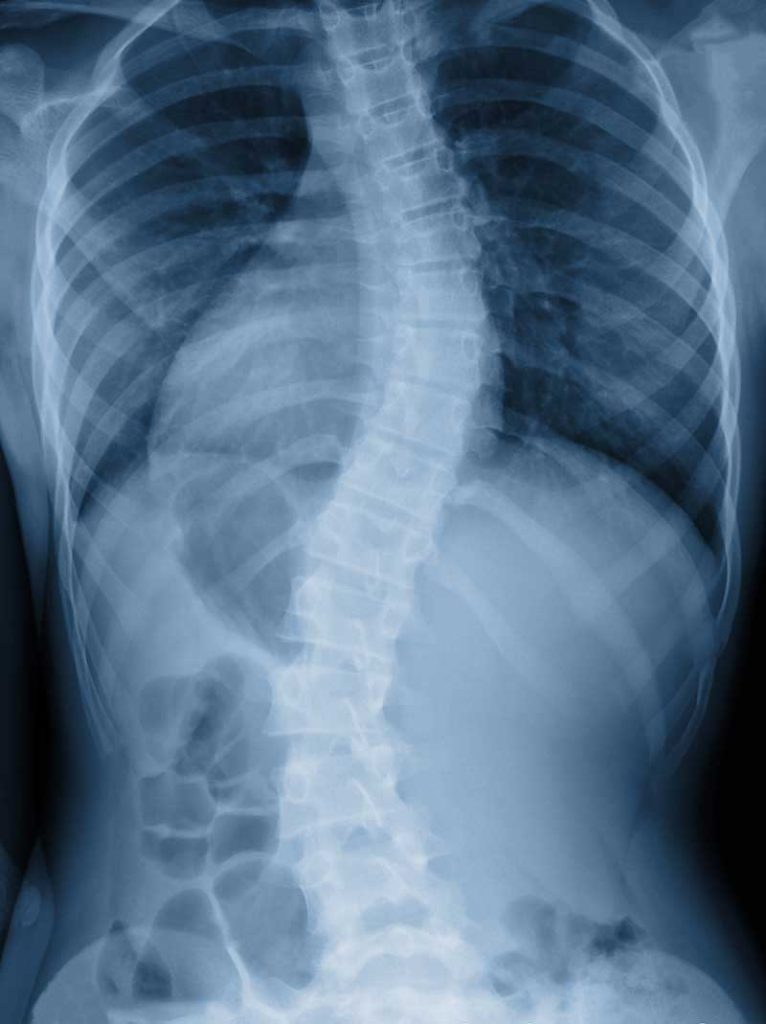

Scoliosis treatment for adults or teenagers can be different than you think. At Whole Body Cures we use non-surgical methods. Non-invasive scoliosis treatment should included in any scoliosis treatment program.

Scoliosis does not have a quick fix. A good scoliosis specialist will not use an overly simplistic one-cause/one-cure methodology. Scoliosis treatment in adolescents is not just daily exercises or stretches. Successful scoliosis treatment requires a comprehensive step-by-step plan.

Scoliosis is not just a misalignment that needs stretching. A scoliosis specialist does not make the correction with muscle strengthening exercises alone. Teen scoliosis treatment and scoliosis prevention must address root cause neurology, including the brain’s ability to set muscle tone. Our plan includes the causal factors contributing to spinal curvature in the first place. So we address: subtle alterations in brain function, spinal mechanics, the neuro-emotional, environmental, and internal cofactor aspects. We don’t limit scoliosis treatment to only the mechanical factors, like with: exercises, spinal adjustments, and stretching.